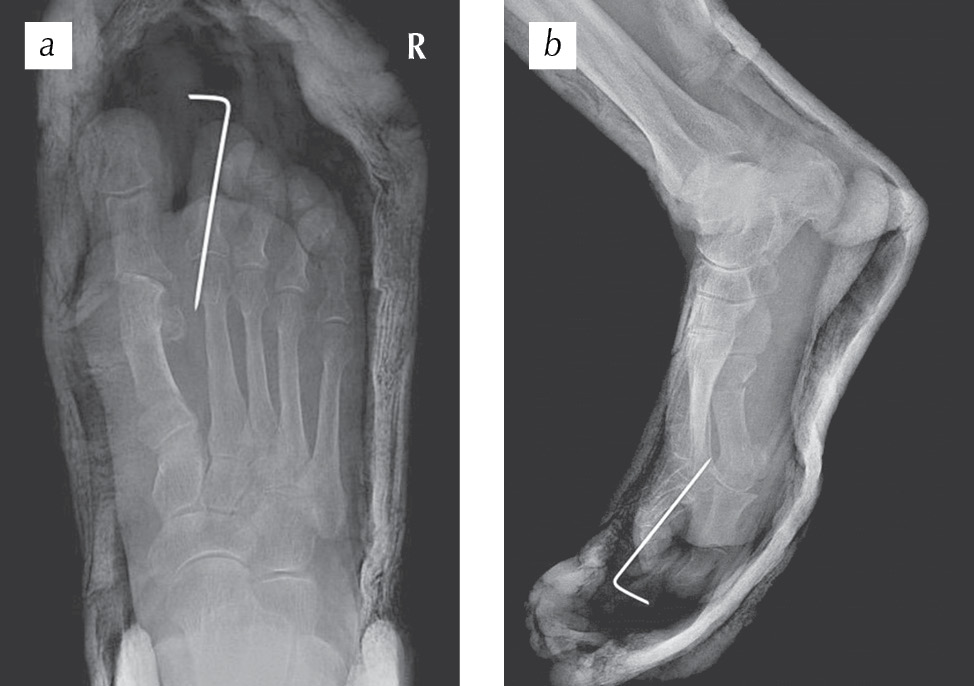

Пациентка Е., 73 года, поступила в отделение травматологии и ортопедии Покровской больницы в плановом порядке с жалобами на деформацию правой стопы, боль при ходьбе (рис. 1). Со слов пациентки, боль, дискомфорт в области правой стопы беспокоят в течение многих лет. В последние два года отмечала выраженные проблемы с ношением и подбором обуви. После обследования установлен диагноз: «Поперечное плоскостопие: hallux valgus правой стопы. Молоткообразная деформация II пальца правой стопы». На рис. 2 представлены рентгенограммы пациентки до оперативного лечения. Угол вальгусного отклонения I пальца, образованный осями I плюсневой кости и проксимальной фаланги I пальца, равен 40° при норме 8–16°. Межфаланговый угол I пальца, образованный осями проксимальной и дистальной фаланг I пальца, равен 0° при норме 0–8°. Угол варусного отклонения I плюсневой кости, образованный осями I и II плюсневых костей, составил 23° при норме 5–14°. Угол наклона суставной поверхности головки I плюсневой кости, образованный осью I плюсневой кости и осью, проведенной перпендикулярно линии, соединяющей края суставной поверхности головки I плюсневой кости, равен 20° при норме 3–10°. Угол наклона суставной поверхности основной фаланги к ее оси, образованный проксимальной фалангой I пальца и перпендикуляром к плоскости суставной поверхности этой же фаланги, равен 3° при норме 0–5°. Угол наклона суставной поверхности медиального плюснеклиновидного сустава, определяемый как угол между линией данного сустава и перпендикуляром к тангете медиального края медиальной клиновидной кости, равен 20° при норме 0–20°.

Рис. 1. Рентгенограммы пациентки Е. до оперативного лечения (выраженный костно-хрящевой экзостоз головки I плюсневой кости, вальгусная деформация I пальца, молоткообразная деформация II пальца с омозолелостью на тыле проксимального межфалангового сустава)

Fig. 1. Radiographs of patient E. before surgical treatment (pronounced bone-cartilage exostosis of the head of I metatarsal bone, valgus deformity of the first toe, hammer-like deformity of the second toe with homosoleness on the back of the proximal interphalangeal joint)

Рис. 2. Рентгенограммы переднего отдела правой стопы пациентки Е. до оперативного лечения: а — прямая проекция; b — косая (3/4) проекция (пояснения см. в тексте)

Fig. 2. Radiographs of the anterior part of the right foot of patient E. before surgery: a — straight projection; b — oblique (3/4) projection (see the text for explanations)